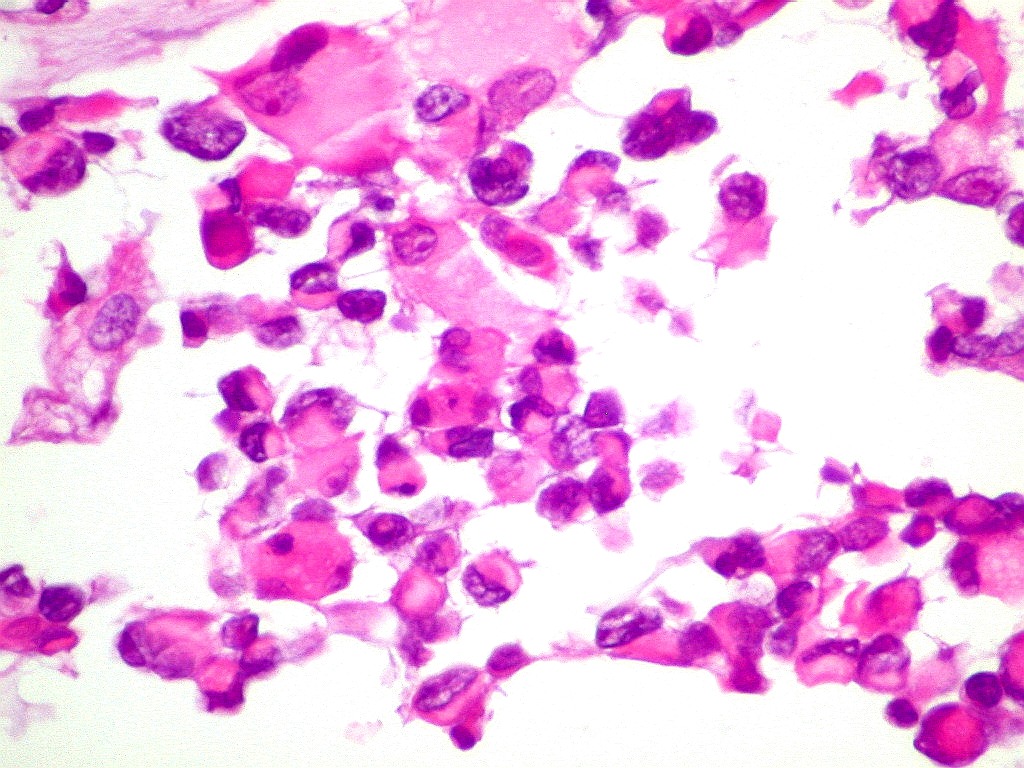

| CD3.

Marcador de linfócitos T, positivo no folículo linfóide,

negativo no tumor. |

CD20.

Marcador de linfócitos B, positivo no folículo linfóide,

CD68.

Marcador de macrófagos, positivo no tumor. Parte da positividade

refere-se a macrófagos, parte às células neoplásicas. |